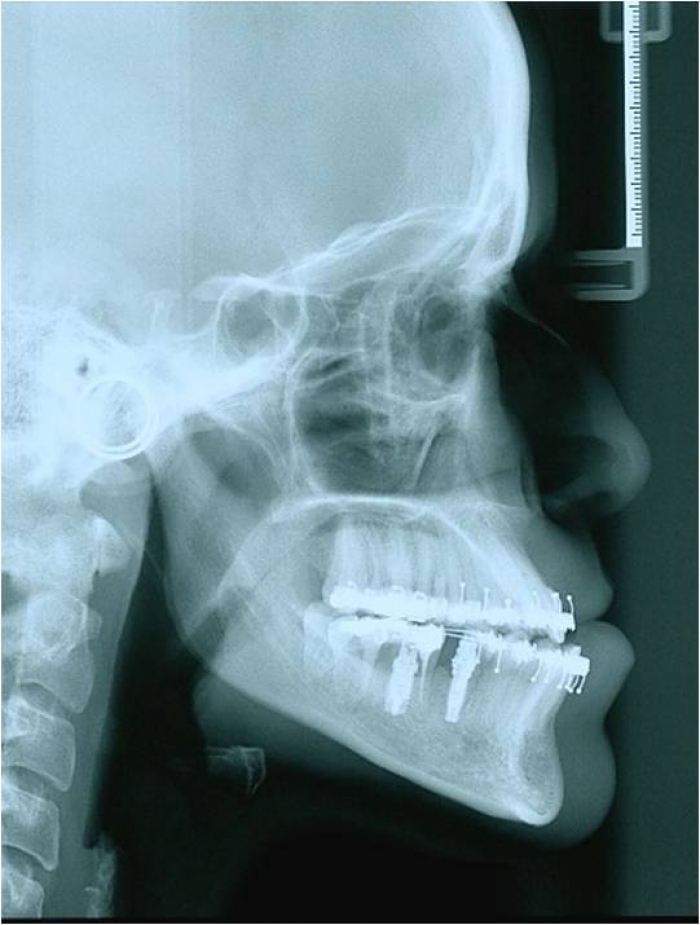

Telerradiografia inicial

Telerradiografia após a cirurgia